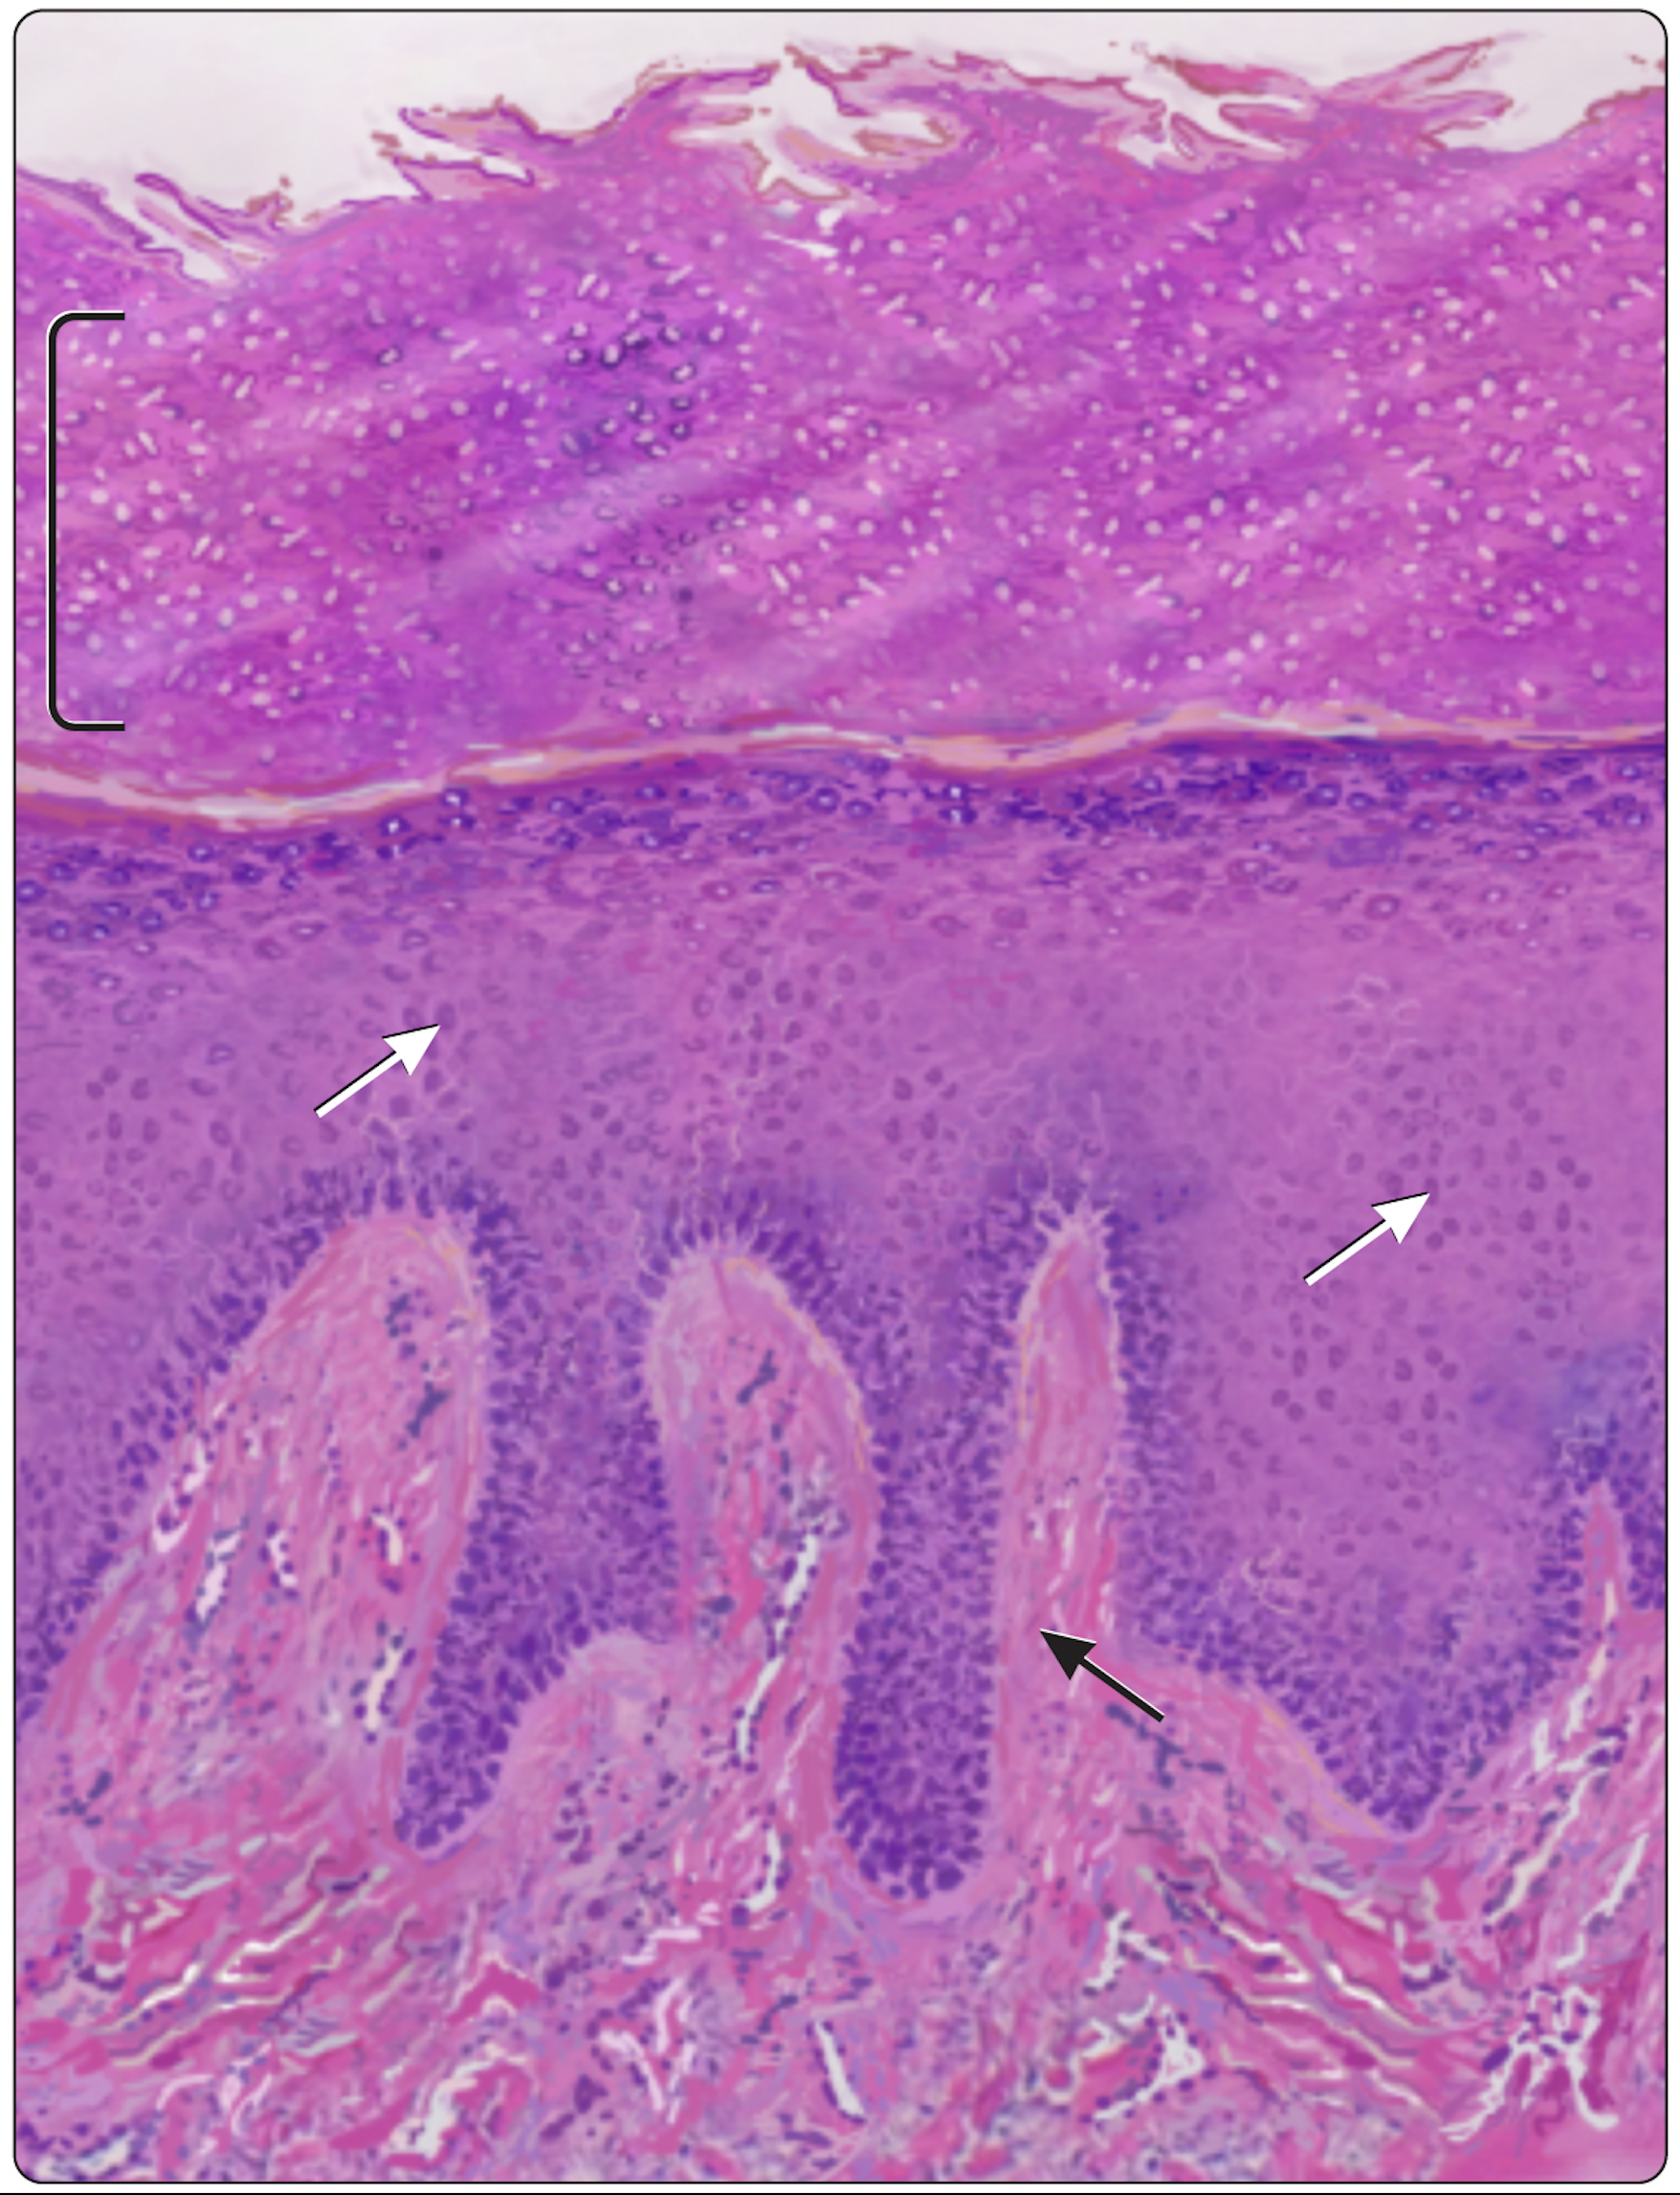

The illustration team has created over 3,000 images! I look through them and find the best assets (whether that’s existing or I go and create it) to use, and then I cobble them together in g-slides and we go through the process of creating an image based on the science writer’s feedback.